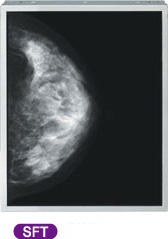

たとえば、近年急速に進展している医療のIT化において、デジタル表示装置の担う役割は大きくなっていますが、これにともない非常に高度な画像再現能力が求められるようになっています。中でも、胸部X線写真やマンモグラフィの読影診断用途では、300万画素を超える高解像度、正確で滑らかな階調特性を実現するための輝度ダイナミックレンジ、視角に依存しないガンマ特性などが必須条件となります。

Tianma Japanは、高い視野角特性を誇るSFT技術をベースに、高輝度を維持しつつ超高精細化を実現することによって、このような医療分野の厳しい要求にもお応えします。